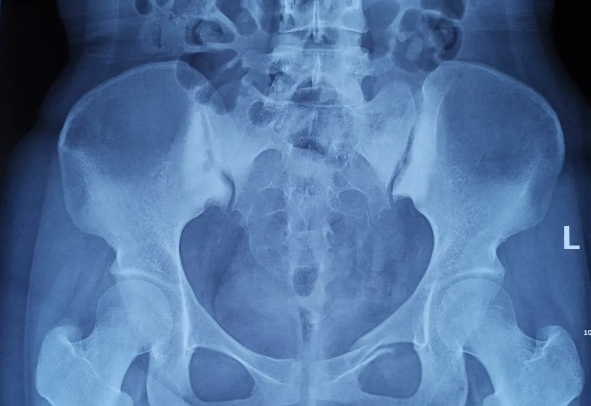

外傷致骨盆骨折

傳統(tǒng)手術(shù)方式切口大

患者為22歲年輕女性,因車禍致骨盆骨折。骨盆骨折是一種復(fù)雜的創(chuàng)傷,傳統(tǒng)手術(shù)方式需要比較大的切口,而且骨盆內(nèi)有大量復(fù)雜血管和神經(jīng),手術(shù)難度和風(fēng)險(xiǎn)極大,是很多骨科醫(yī)生的禁區(qū)。